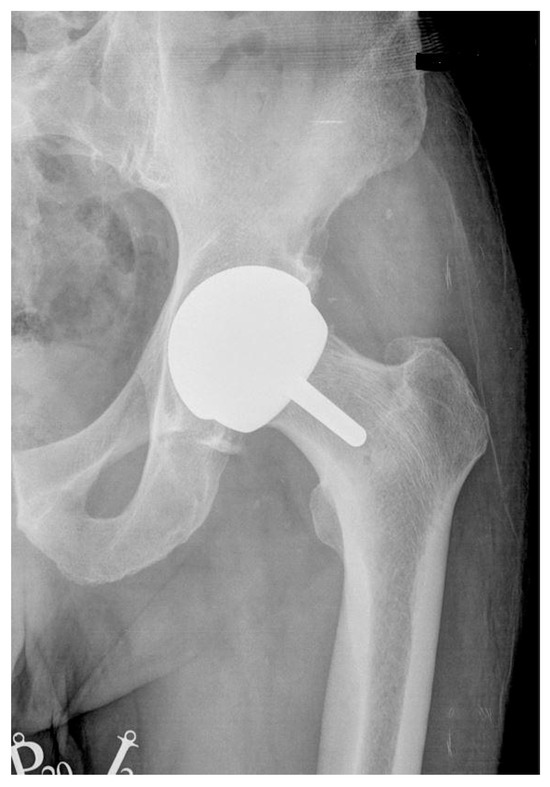

2.1. Description of the Studied Groups and Implants Used